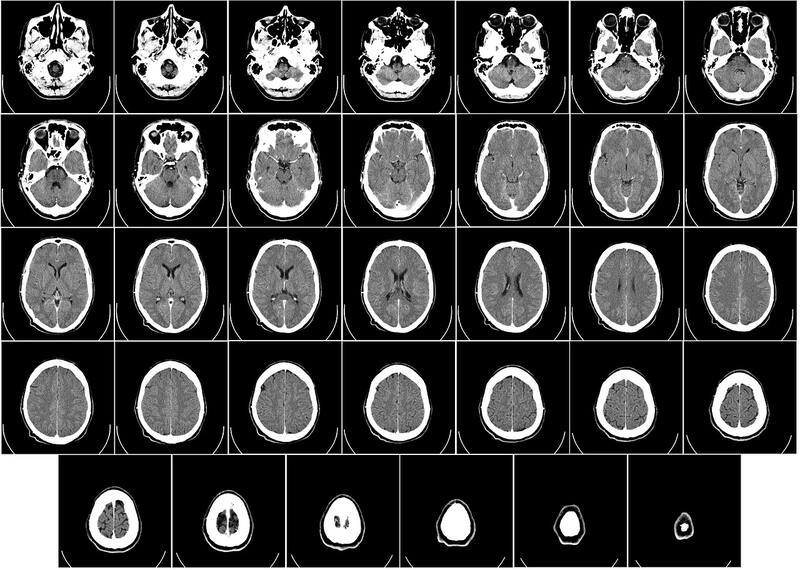

Los investigadores analizaron tomografías computarizadas en 120 pacientes neurológicos, incluidos 58 con Covid-19 agudo y 62 sin Covid-19, emparejados por edad, sexo y enfermedad. El trabajo se realizó conjuntamente con Enrico Premi y sus colegas de la Universidad de Brescia (Italia), que proporcionaron los datos para el estudio. Utilizaron un análisis de morfometría basado en la fuente, que aumenta la potencia estadística de los estudios con un tamaño de muestra moderado.

El análisis mostró que los pacientes con mayores niveles de discapacidad tenían un menor volumen de materia gris en los giros frontales superior, medial y medio en el momento del alta y seis meses después, incluso cuando se controlaban las enfermedades cerebrovasculares.

El volumen de materia gris en esta región también se redujo significativamente en los pacientes que recibían oxigenoterapia en comparación con los que no la recibían. Los pacientes con fiebre presentaron una reducción significativa del volumen de materia gris en los giros temporales inferior y medio y en la circunvolución fusiforme en comparación con los pacientes sin fiebre. Los resultados sugieren que la Covid-19 puede afectar a la red frontal-temporal a través de la fiebre o la falta de oxígeno.